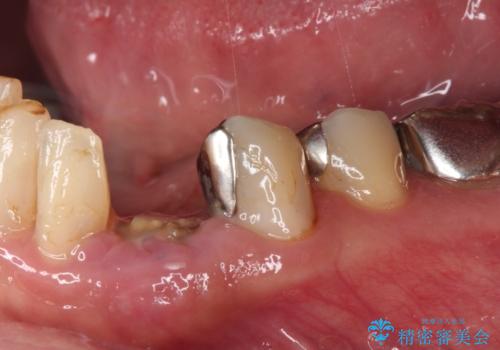

- クラウンがもげてしまった歯が抜歯と言われたとのことで来院された患者様です。

根管治療がされた歯であり、唇側に転位していたため、力がかかったことでクラウンが外れてしまったと判断されました。

麻酔下で歯肉を開いて診察をしたところ、唇側の歯肉縁下に深く歯が欠けている状態でした。